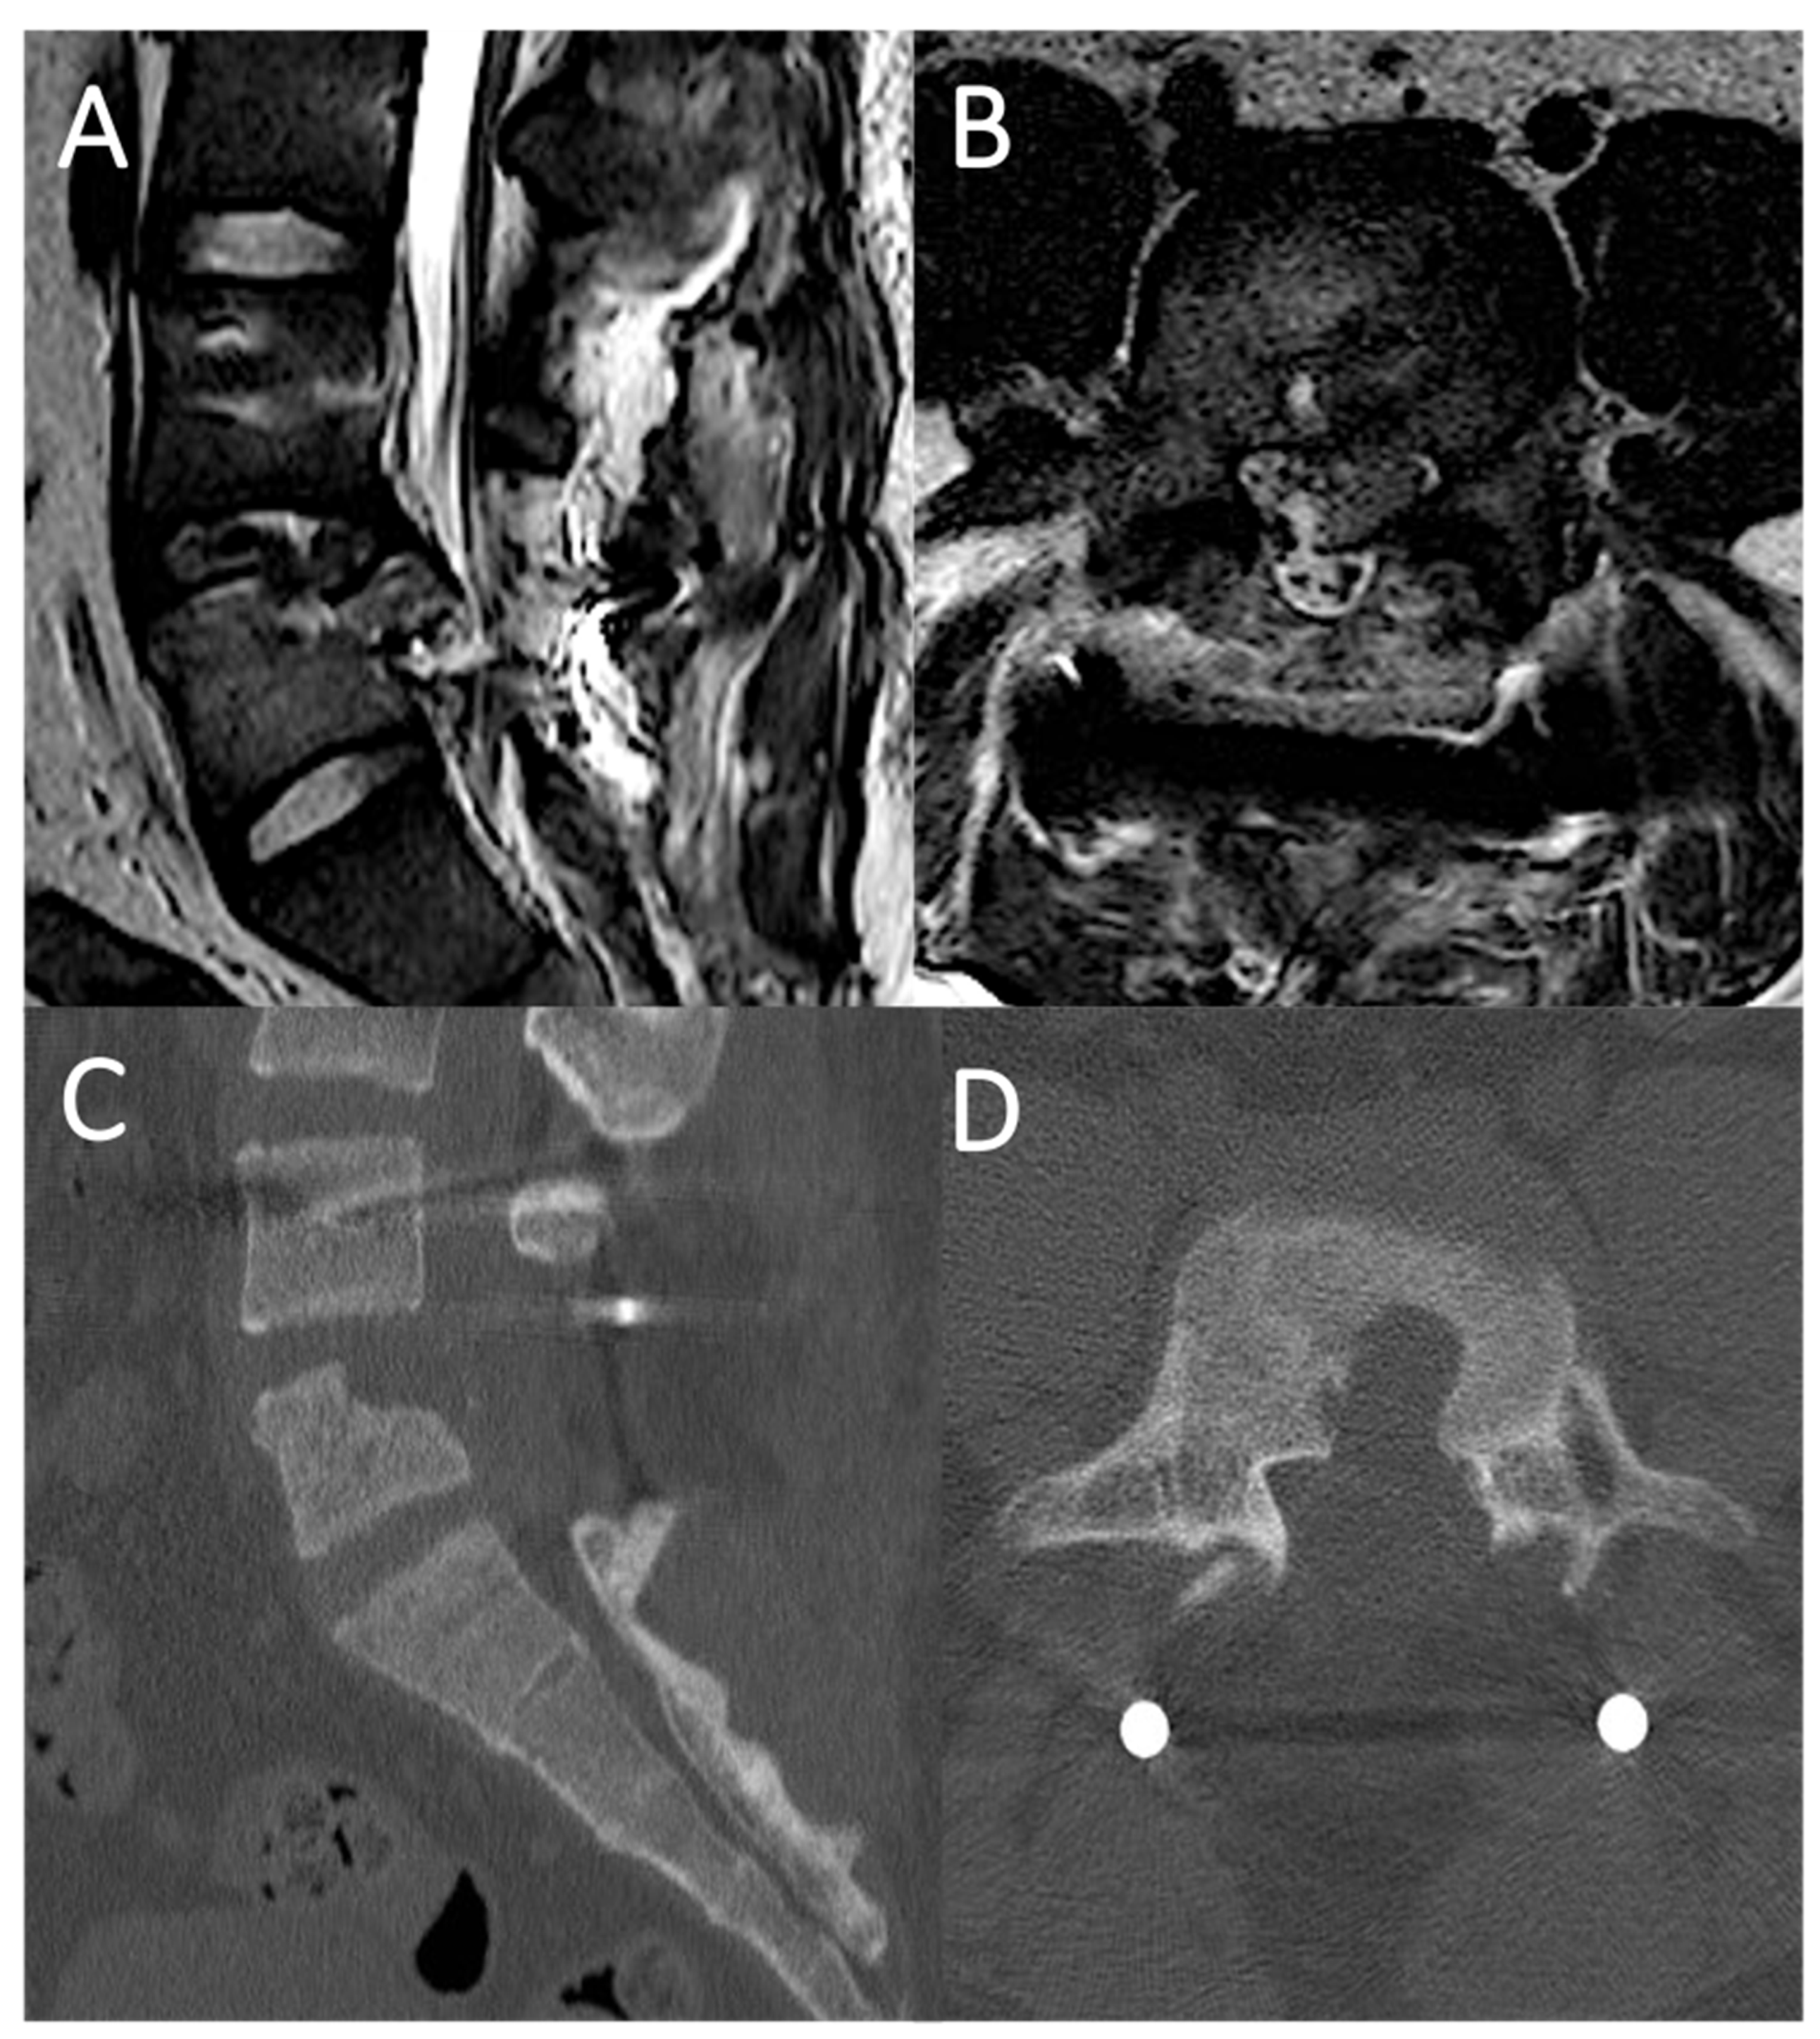

4.2. Case Report 2: Coating Straddling Nerve Roots

4.3. Case Report 3: Coating with Sutured Fat Graft